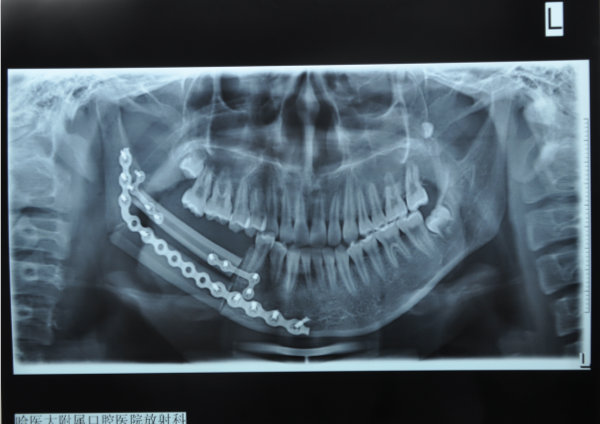

经过近8个小时的手术,将病变下颌骨连同肿瘤完整切除,把腓骨瓣移植到口腔重建了下颌骨,显微血管进行了吻合,恢复了下颌骨的连续性与面部轮廓,术后恢复顺利。已于10天后出院康复治疗。经过2个月随访,病人已经能够正常进食,下肢取骨术区恢复良好,可以日常活动。

王德明副主任医师介绍,按照治疗计划,一年后将为女孩取出内固定钛板,进行种植牙手术,修复缺失的牙齿,最终恢复咀嚼功能,实现颌骨功能与外形重建。